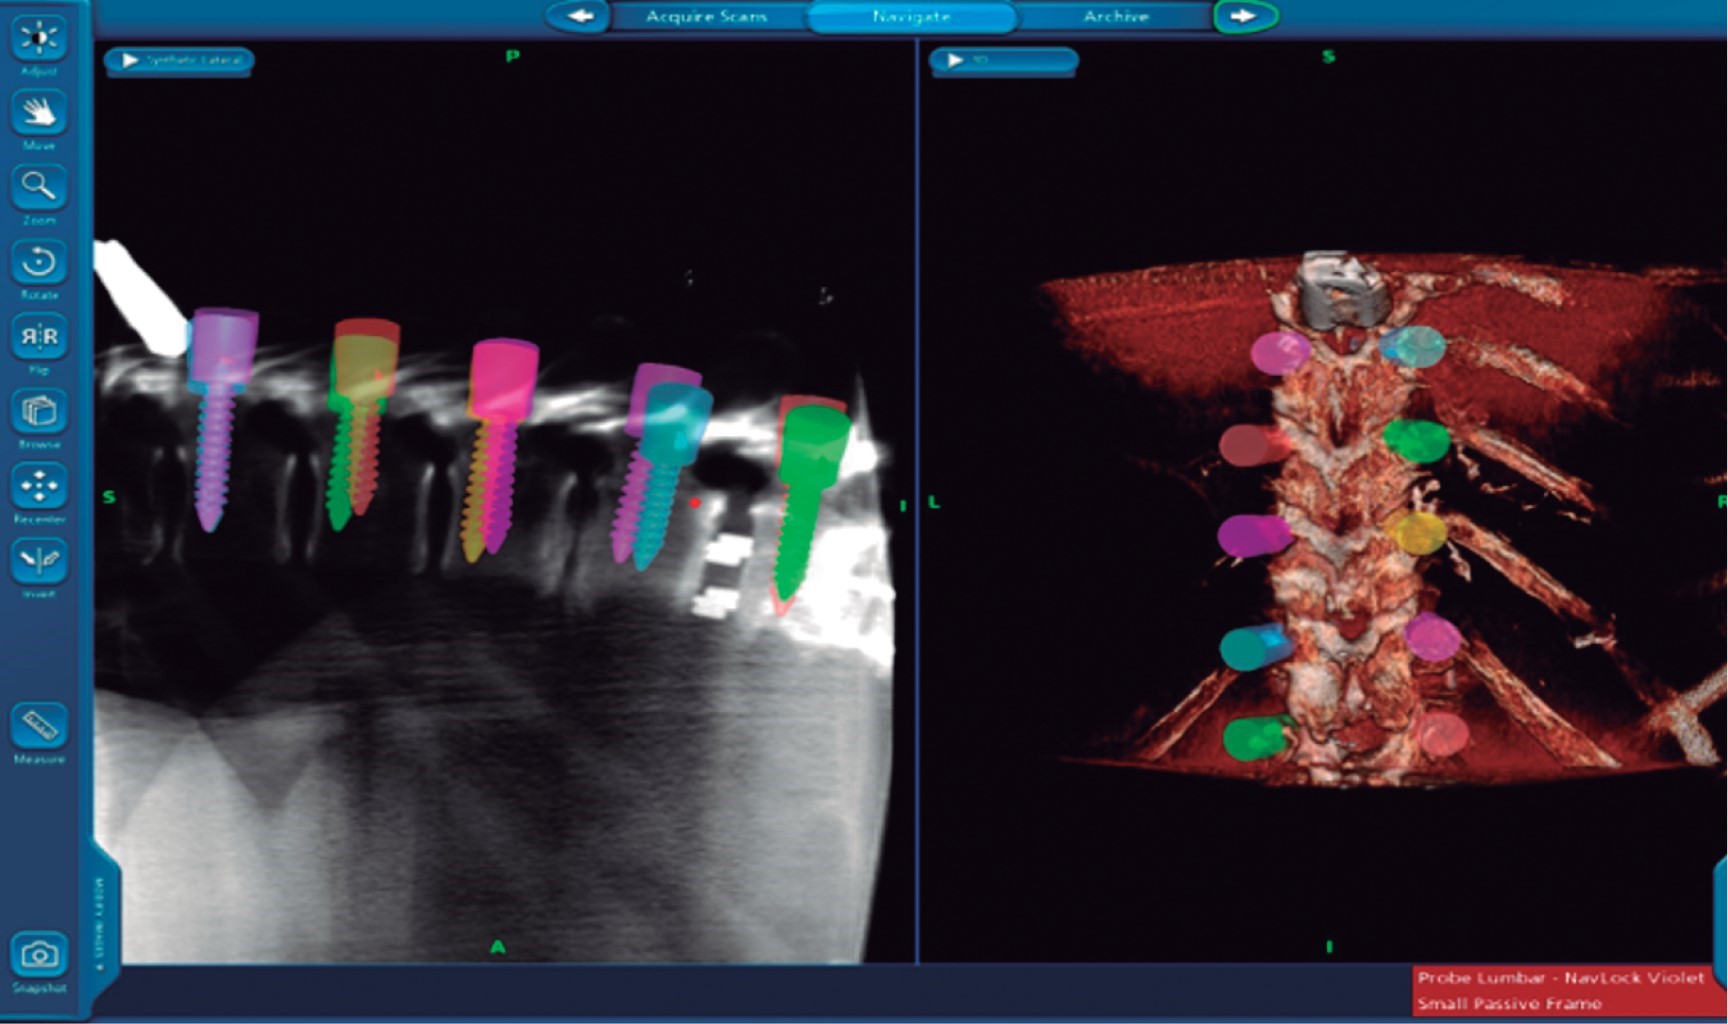

Tratamiento: corrección de escoliosis, mixta XLIF T12 a L4, tornillos pediculares de T9-S1 con navegación O-ARM & StealthStation, (TLIF) de L5-S1 y fusión posterolateral (Figuras 5 y 6).

El uso de O-ARM disminuye prácticamente la exposición a radiación al personal médico y de la sala de quirófano, ya que se realiza un único barrido abarcando cinco segmentos por barrido, lo cual conlleva una radiación de 10 Msv.9 El uso de C-ARM nos da fallas hasta de 20% con rupturas de pedículo mayores a 4 mm en 3.8% de los casos detectados con TAC posterior a evento quirúrgico.10 Un 97.5 a 99% de los tornillos colocados con navegación se ponen correctamente (Figura 7).

La asociación de O-ARM con lesión nerviosa va de 1-3%. Con el uso de C-ARM está estimada la falla de colocación de tornillos en segmentos largos hasta de 41% (G0-G1-G2-G3-G4). Con el O-ARM, el mayor desplazamiento que se espera es un G0-1 < 2 mm.3 Con O-ARM el tiempo estimado de colocación de tornillo es de 2-8 min. A diferencia de C-ARM (15-20 min) en O-ARM (Figuras 8 y 9). Como limitación, existe el costo y la diferencia medida con el punzón del tornillo real 3.14 mm. Se ha reportado que de cada 436 tornillos colocados, sólo existen 4 fallas cuando se unen O-ARM Y NAVEGACION (0.9%), y aun así, demuestra una baja probabilidad de lesión nerviosa al ser colocados como G0-G1 (Figura 10).

Figura 5

Figura 6

Figura 7

Figura 8

Figura 9

Figura 10